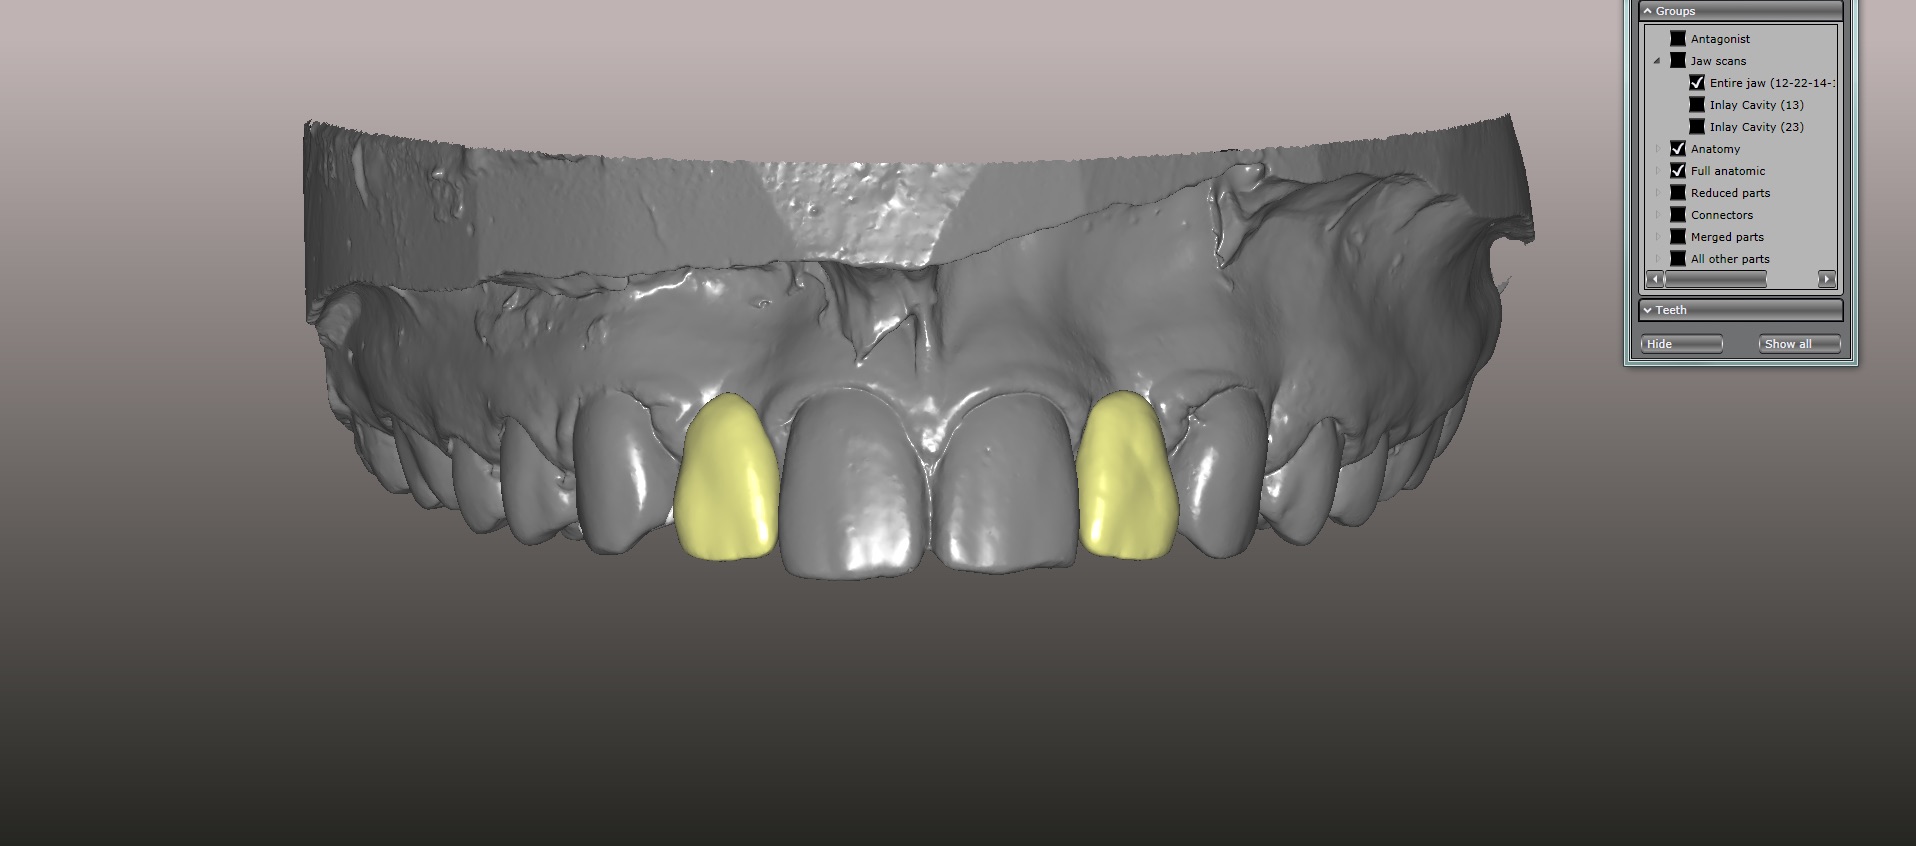

(15.) Models mounted in maximum intensity projection, allowing design of the retainer extensions on the lingual of the canines (in pink).

Figure 15

An approach utilizing CAD/CAM was employed to fabricate an accurate fitting, retentive, and esthetic ceramic single-wing resin-bonded bridge. Impressions were taken of the patient and scanned in the laboratory using maximum intensity projection. The scanned models were then used to design the final prosthetic frames utilizing EXOCAD software. The retainer positions and extensions were designed on the models based on the occlusal clearance (Figure 15). Next, the replacement tooth forms were chosen from a virtual library (Figure 16), and try-in PMMA bridge prototypes were milled in Primotec USA PMMA. This allowed for try-in of the design, adjustment of the contacts, and intraoral evaluation of the ridge contact (Figure 17). Once tried and idealized for both fit and occlusion, the design was sent back to the lab to rescan. Utilizing the software, a cut back was made on the lateral incisor (Figure 18), and a 0.3mm space was also virtually designed on the internal surface of the retainer wing to allow layering with feldspathic ceramic (Figure 19). The 0.2 mm internal edge of the wing was designed to be left intact to allow for precise seating and verification of fit on the model. After the frame was milled in zirconia (Zirconzahn, Prettau), it was verified on the model, and high fusing margin porcelain (Noritake CZR) was mixed with a clear utility wax and applied to the internal 0.3 mm depression. This was baked in the oven at a high temperature, allowing the wax to burn out and leaving the feldspathic ceramic fused to the internal surface of the retainer. Once cooled, this was checked for precise fitting on the model and adjustments were made to ensure full seating.